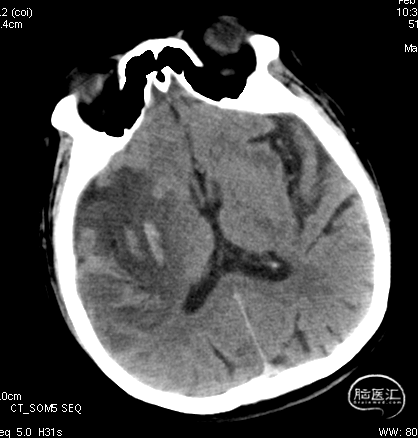

急诊颅脑CT+CTA:无脑出血,ASPECTS评分:7分;CTA示右侧M1闭塞。

急诊颅脑CT+CTA

局麻,右股动脉入路置8F短鞘,导管导丝技术将8F MPA置于右C1末端,造影确认右M1急性闭塞,侧支代偿差。

以Transend导丝 + Headway21导管到达M1中段,Sofia PLUS顺畅到位(M1中段),ADATP技术抽吸取栓,一次成功取通,前向血流恢复至TICI3级,无栓子逃逸及原位狭窄,穿刺至开通时间20min(患者术中间断躁动不配合)。

以Sofia Plus进行抽吸取栓1次(ADAPT技术),实现血流复通(TICI 3级)